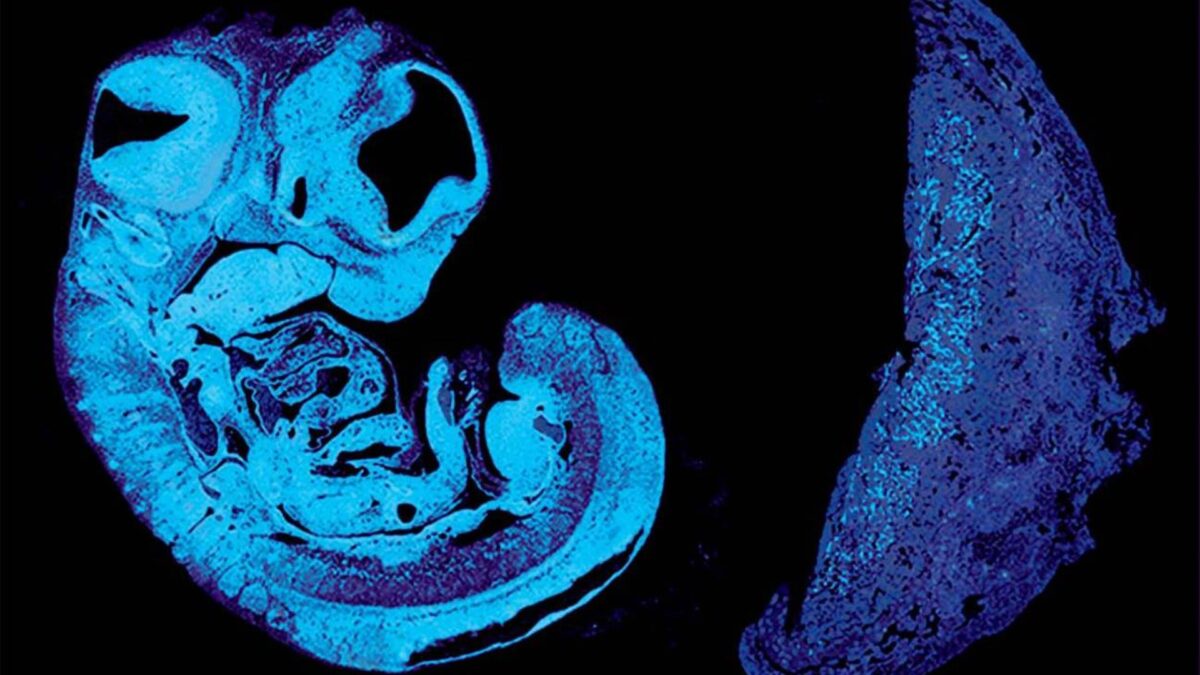

A la izquierda se observa la sección de un feto de ratón y a la derecha la placenta. | Ionel Sandovici

El feto recibe alimento a través de los vasos sanguíneos de la placenta, un órgano especializado que contiene células tanto del bebé como de la madre. A medida que este crece, su demanda nutricional es mayor.